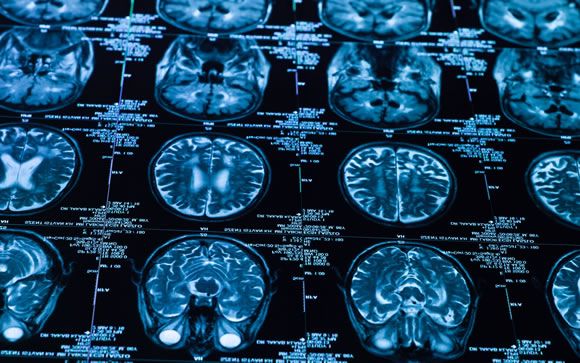

Desde un punto de vista sanitario y socioeconómico, el ictus es un problema de primera magnitud. En los últimos 15 años, el número de pacientes atendidos en hospitales del Sistema Nacional de Salud (SNS) por enfermedades cerebrovasculares ha aumentado un 40%, lo que ha hecho que las enfermedades cerebrovasculares sean ya la octava causa de hospitalización. Actualmente, es la entidad neurológica que mayor número de ingresos hospitalarios genera en España (el 70% de los ingresos neurológicos) y una de las patologías que requieren de mayor estancia hospitalaria y, consecuentemente, de mayor coste para los sistemas sanitarios. El ictus, es responsable del 3 al 6% del gasto total sanitario.Además, aunque en los últimos 20 años se registra una tendencia a la baja en la mortalidad gracias a los trabajos de prevención, detección precoz y mejora de la atención neurológica especializada hospitalaria, las enfermedades cerebrovasculares son las causantes del 8% del total de defunciones en hospitales del SNS. “Es evidente, dada la magnitud del problema, la necesidad de establecer una adecuada política de prevención, junto a la implantación de modelos organizativos de asistencia al ictus con el objetivo de disminuir la mortalidad y además reducir sus secuelas. Sobre todo porque además se espera un aumento de la incidencia y prevalencia de esta enfermedad en los próximos años debido al progresivo envejecimiento de la población”, señala el coordinador del Grupo de Estudio de Enfermedades Cerebrovasculares (GEECV) de la Sociedad Española de Neurología (SEN), Jaime Gàllego Culleré.

Uno de los principales avances de la medicina clínica y la salud pública de la última década ha sido la demostración de que una atención neurológica especializada y urgente en Unidades de Ictus (UI) mejora la evolución de los pacientes que lo han sufrido. De acuerdo al nuevo informe “Observatorio sobre la atención de la patología cerebrovascular en España” elaborado por el Grupo de Estudio de Enfermedades Cerebrovasculares (GEECV) de la Sociedad Española de Neurología (SEN), en nuestro país hay en la actualidad 57 Unidades de Ictus y se espera la próxima apertura de otra más en Galicia. Actualmente todas las comunidades autónomas disponen del protocolo de actuación denominado “Código Ictus” y todas disponen de, al menos, una Unidad de Ictus. Sin embargo, aún existen 19 provincias sin Unidad de Ictus, además de las dos ciudades autónomas, a pesar de que alguna de ellas tiene una población superior a los 250.000 habitantes.